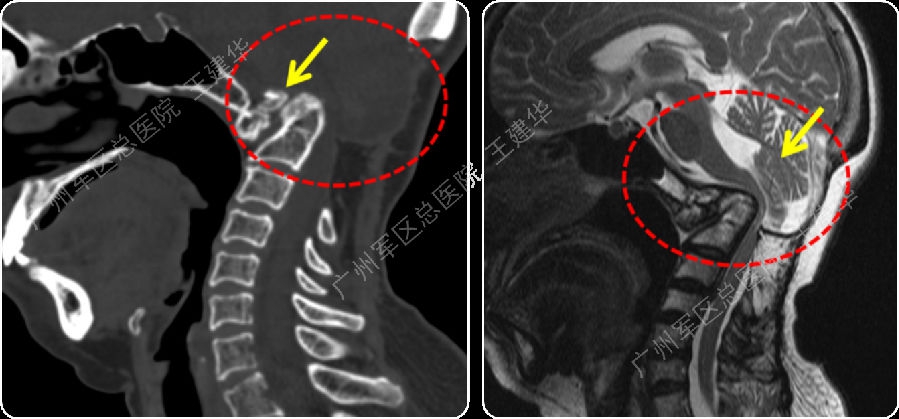

三维CT显示患者合并寰枕融合及C2/3融合,颅底凹陷

本例患者手术过程

手术前后对比

手术后2年复查的CT,显示侧块关节已经完全融合

病例4

颈椎MR检查提示:颈椎上端结构陷入枕骨大孔,脑干受压变形

手术复位过程

手术完成

可以看到:

陷入枕骨大孔的寰椎和齿突已经下拉复位,枕颈排列恢复正常

脑干压迫解除,延髓脊髓角恢复正常

手术后6年复查:

颅颈椎序列恢复正常并骨性融合